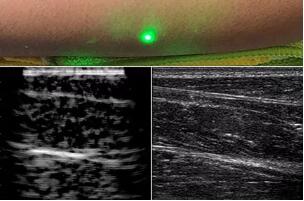

臨床應(yīng)用的無創(chuàng)超聲,要求探頭與人體皮膚直接接觸來向身體傳導高頻振動的超聲波。但是,有一些特定的患者卻在超聲檢查時受到限制,比如兒童、燒傷患者和敏感皮膚患者等。而近日麻省理工學院的研究人員證明,確實有可能使用激光在不接觸皮膚的前提下對患者進行超聲波掃描。

一般的光聲成像涉及使用激光在組織內(nèi)感應(yīng)聲波,并通過仍然需要進行物理接觸的檢測器拾取超聲反射。而且,這樣的掃描僅在非常淺的深度起作用,僅在皮膚以下幾毫米處有效成像。

而麻省理工學院的研究小組現(xiàn)在開發(fā)了一種使用激光檢測皮膚上超聲波振動的方法,以便可以使用一種激光使皮膚產(chǎn)生共振,而另一種則可以檢測到振動,從而達到“遠程超聲掃描”的作用。

這一發(fā)現(xiàn)極具重量,該技術(shù)甚至有可能會讓超聲診斷領(lǐng)域發(fā)生革命性的變化。不只是特殊患者群體能夠因此受益,由于傳統(tǒng)的超聲診斷,會因為皮膚接觸而嚴重調(diào)制所得信號,因此無接觸方法可以完全克服該限制,這使得該技術(shù)能夠有更廣的應(yīng)用場景。

目前,研究人員已經(jīng)與健康的志愿者測試了他們的系統(tǒng):從半米遠處掃描了他們的前臂,并將這些結(jié)果與傳統(tǒng)超聲的結(jié)果進行了比較。他們能夠觀察到深達6厘米的組織,并能看到肌肉,脂肪和骨頭,并報告其結(jié)果可與標準超聲相媲美。

麻省理工學院機械工程系和醫(yī)學工程與科學研究所(IMES)的首席研究科學家布萊恩·安東尼(Brian W. Anthony)說:“我們是激光超聲技術(shù)的開端?!痹撗芯堪l(fā)表在《Light: Science & Applications》雜志上。 “想象一下,我們已經(jīng)達到了超聲波現(xiàn)在可以做的所有事情的地步,但要保持一定距離。這為您提供了一種全新的方式來查看體內(nèi)器官并確定深層組織的性質(zhì),而無需與患者接觸?!?/span>

根據(jù)他們的研究,該團隊選擇了1,550納米激光器,該波長被水高度吸收(并且對眼睛和皮膚安全,并具有較大的安全裕度)。由于皮膚基本上是由水組成的,因此研究小組認為皮膚應(yīng)該有效吸收這種光,并因此而變熱并擴張。當其振蕩回到其正常狀態(tài)時,皮膚本身應(yīng)產(chǎn)生通過身體傳播的聲波。

研究人員用一種激光裝置測試了這個想法,該裝置使用一個波長為1,550納米的脈沖激光來產(chǎn)生聲波,并使用第二個連續(xù)激光,調(diào)諧到相同的波長以遠程檢測反射的聲波。第二個激光器是靈敏的運動檢測器,可測量聲波從肌肉,脂肪和其他組織反射回來而引起的皮膚表面振動。反射的聲波產(chǎn)生的皮膚表面運動會導致激光頻率發(fā)生變化,這種變化可以測量。通過機械掃描人體上的激光,科學家可以獲取不同位置的數(shù)據(jù)并生成該區(qū)域的圖像。